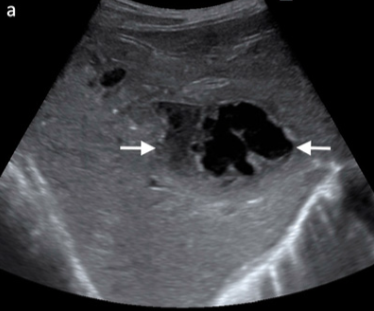

What is Budd–Chiari syndrome, and what are its key clinical findings?

Occlusion of the hepatic veins (± IVC).

Clinical findings: ascites, elevated LFTs, hepatomegaly, splenomegaly, upper abdominal pain.

What are the hallmark sonographic findings of Budd–Chiari syndrome?

Absent or reduced visualization of hepatic veins, thrombus in hepatic veins, absent flow on color Doppler, enlarged caudate lobe, and possible IVC narrowing.

What is the vascular disease in this liver?

Budd-chiari syndrome